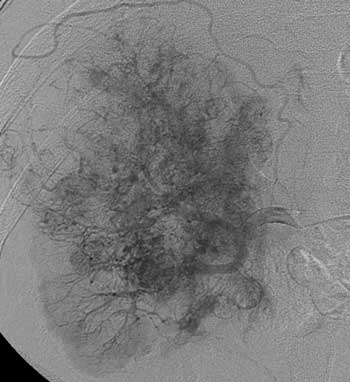

Рис. 3. Рак правой почки Т3bN0M0. Опухолевая васкуляризация «пушистого» вида расположена вдоль ветвей почечной артерии. Опухоль имеет бугристый, нечёткий контур.